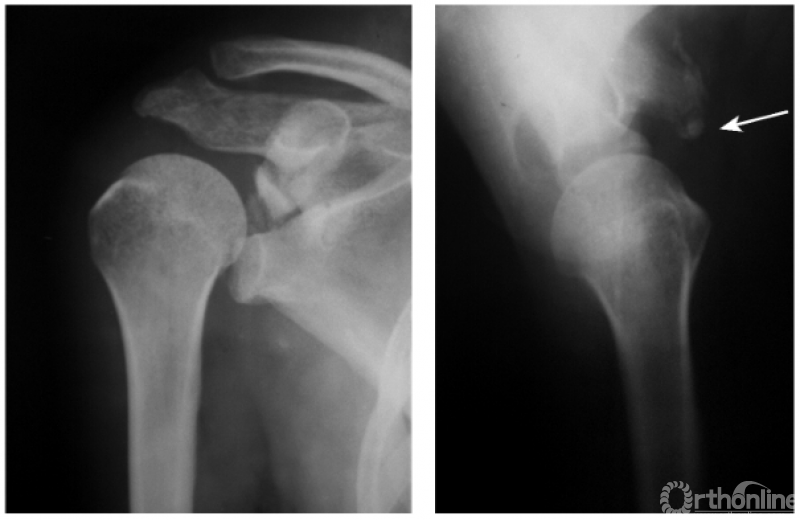

肩关节后脱位是所有大关节脱位中最易误诊的一种损伤,其误诊率可高达60%,因此该病有“诊断的陷阱”之称,有学者指出肱骨头关节面与盂前缘距离大于6mm时应高度怀疑有后脱位的可能。

此外,由于脱位后上臂外旋受限,因此即使在最大外旋位拍片时仍不能显示出肱骨颈及大结节的轮廓。例:肱骨头离开关节盂而向后外上方(肩峰之下)移位且内旋,致肱骨头与肱骨干在一直线上,招致肩肱曲线不流畅,肱骨头关节面与盂前缘距离大于6mm并小结节骨折(如下图)。